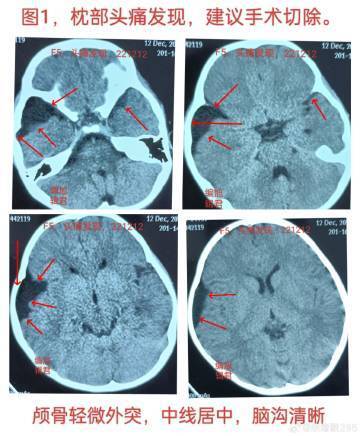

一位6歲的女孩,在5歲時(shí)因頭痛接受CT檢查,發(fā)現(xiàn)右顳部有一個(gè)小的蛛網(wǎng)膜囊腫,見下【圖-1】。在某醫(yī)院就診時(shí),醫(yī)生建議手術(shù)切除,原因是該囊腫可能會(huì)長大、破裂或出血??紤]手術(shù)風(fēng)險(xiǎn),家長選擇觀察治療。一年多后復(fù)查CT,見下【圖-2】,對比兩次檢查結(jié)果,發(fā)現(xiàn)囊腫沒有明顯變化,右顳骨質(zhì)外突未改變,腦中線也未移位,腦溝清晰可見。病案特點(diǎn):1、患者為6歲女孩。2、因頭痛偶然發(fā)現(xiàn)囊腫,目前無任何不適癥狀。3、小囊腫無張力,伴有腦組織發(fā)育不全,腦中線未移位,顱骨輕度外突。4、觀察一年后,囊腫未見明顯變化,患者無不適癥狀。建議:繼續(xù)觀察,定期復(fù)查和對比檢查結(jié)果。